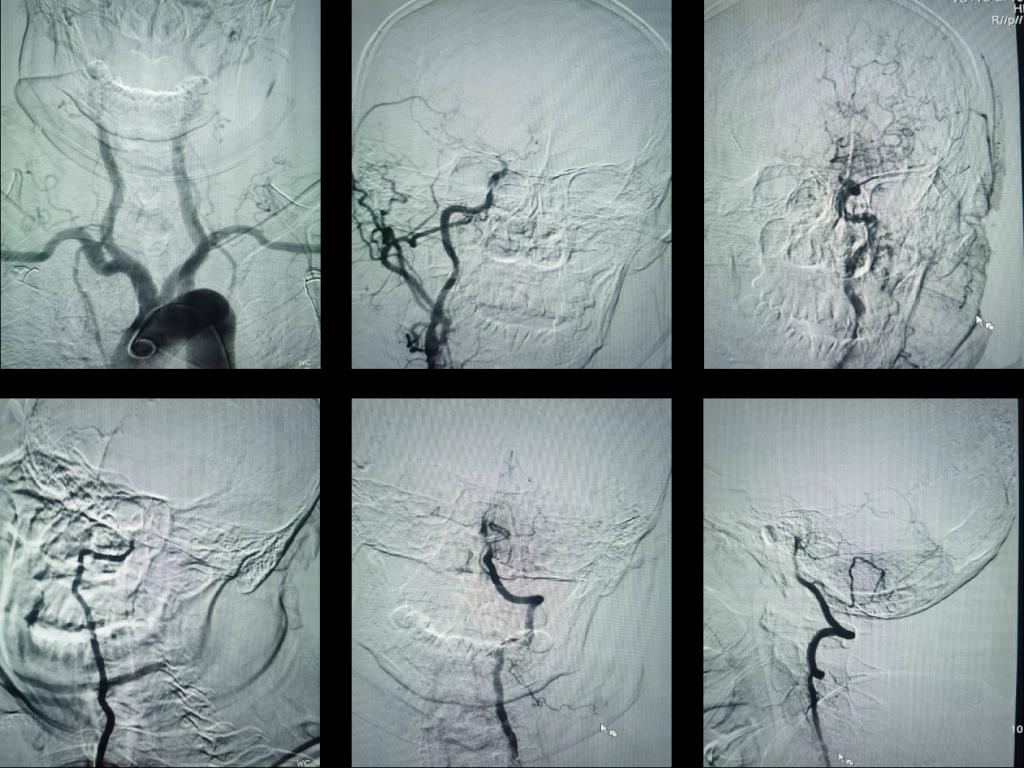

患者洪某,男,68岁,既往长期高血压病史,控制不佳。9小时前晨起时出现头晕伴行走不稳,未重视。5小时前突发意识不清,四肢不能活动,大小便失禁。接诊患者后急诊科、神经内科、影像科及检验科等立即启动脑卒中绿色通道,第一时间完成头颅磁共振,明确诊断急性后循环多发脑梗死,脑桥双侧受累。

图1 头颅磁共振,明确诊断急性后循环多发脑梗死,脑桥双侧受累